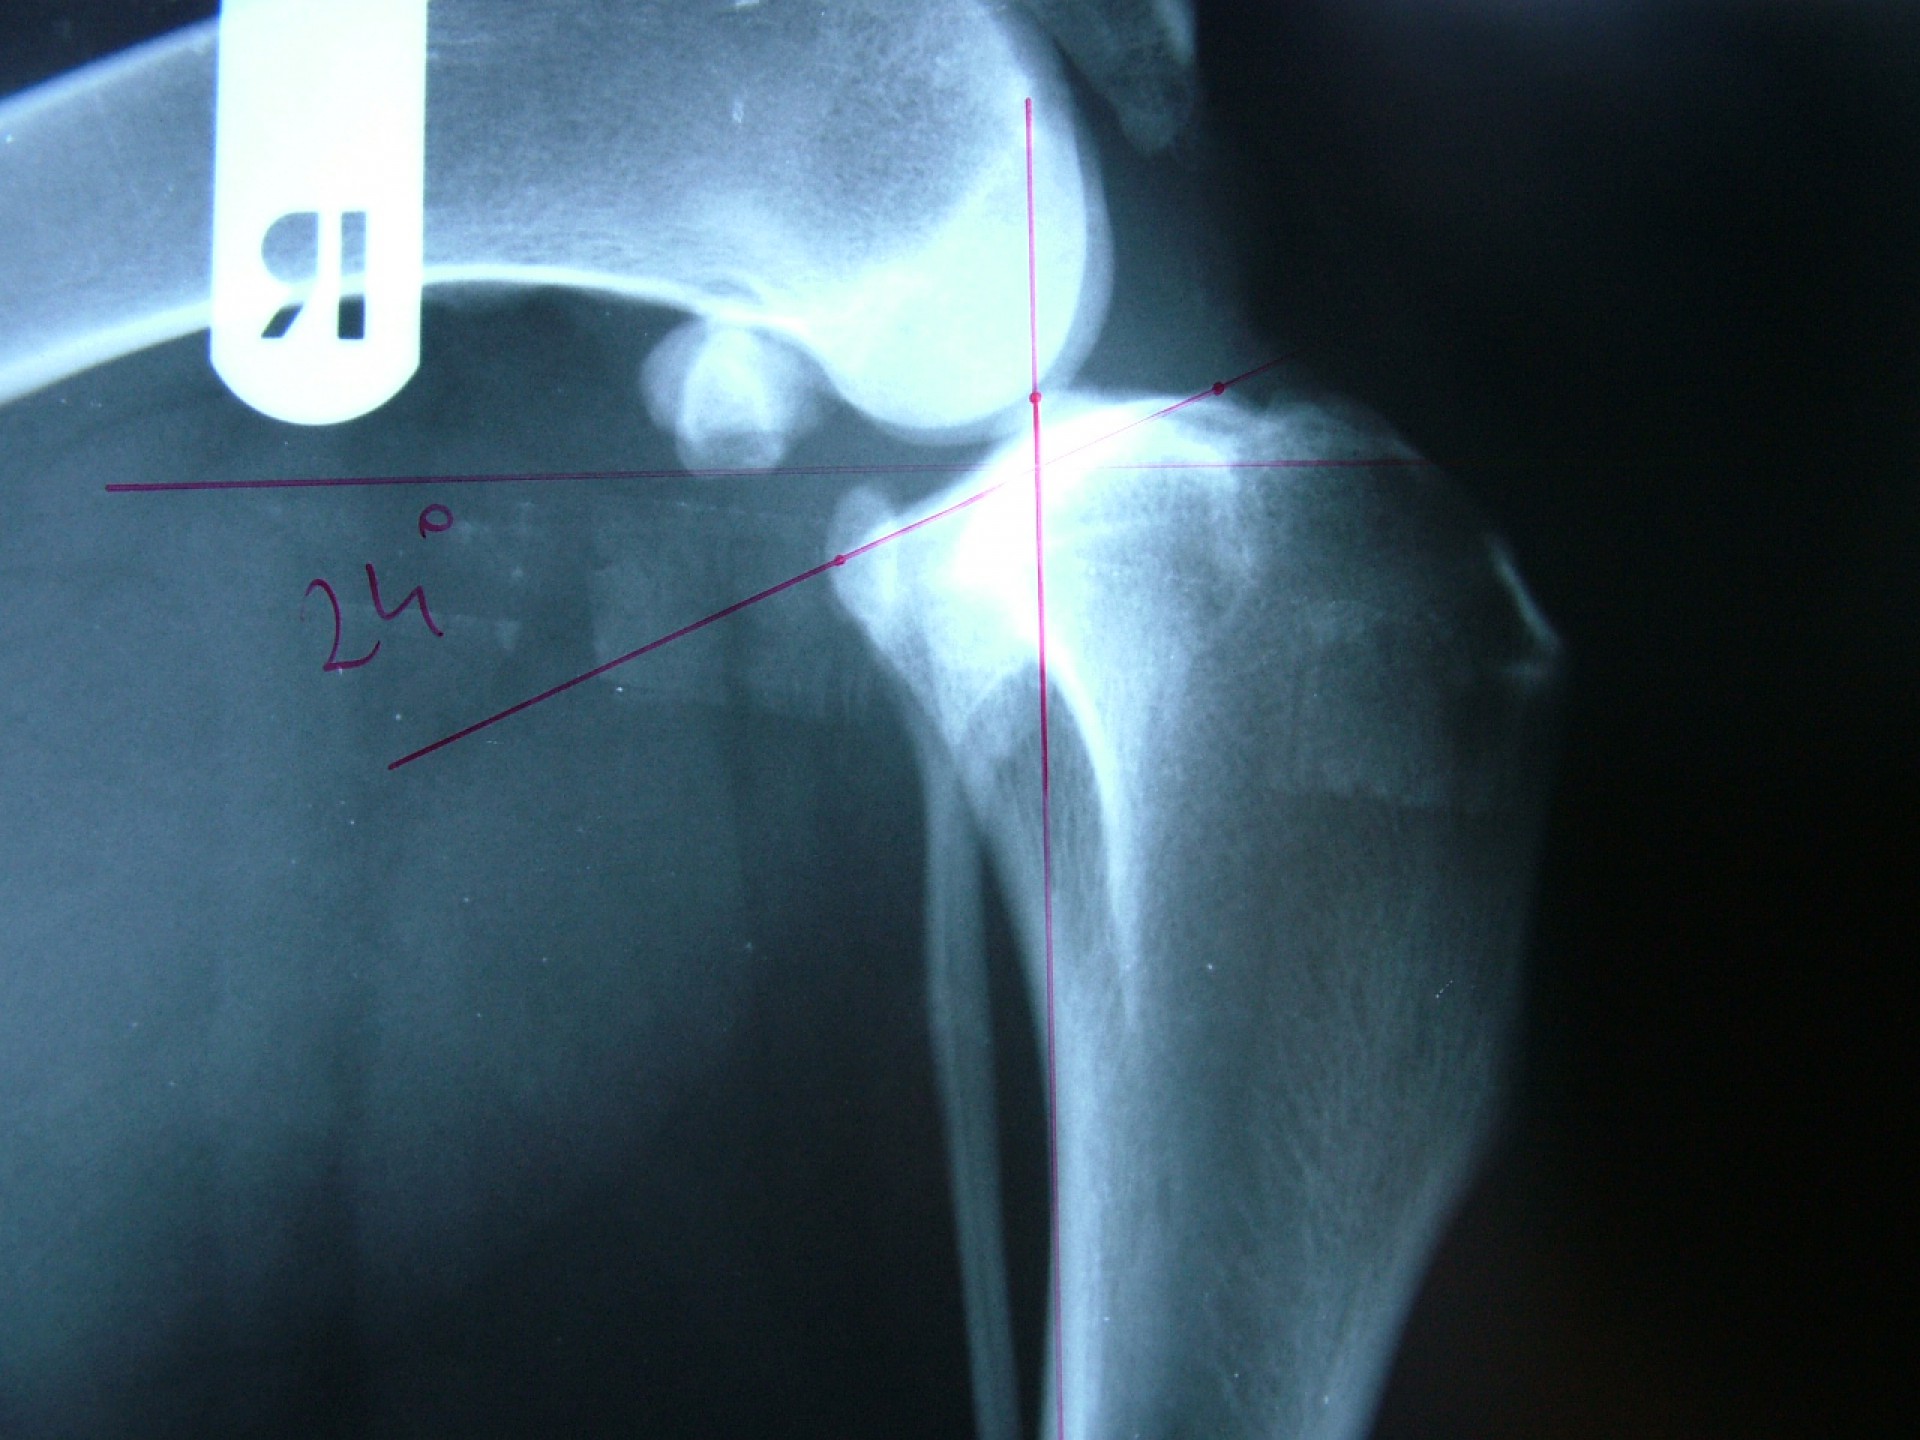

Az utóbbi 25 év egyik legnagyobb előrelépését jelentette a kereszteződőszalag szakadás műtéti megoldásában az amerikai származású Barclay Slocum által kifejlesztett műtéttechnika, mely alapja a szakadásra hajlamosító tényezők és a szalagra ható fizikai erők vizsgálata. Barclay Slocum olyan műtéti technikát dolgozott ki, mellyel a térdízületet az elülső kereszteződőszalagra ható erőkhöz igazítja. Vizsgálatai alapján a sípcsont ízületi felszínének meredeksége (tibia plató szög, tibial plateau angle, TPA) és az elülső kersztezőszalag szakadása között egyértelmű összefüggés mutatható ki. A műtét alapja, hogy a sípcsont ízületi felszínét a sípcsontból kivágott ék, majd azt követő lemezes osteosynthesis segítségével a sípcsont hossztengelyére megközelítőleg merőlegesre állítja be, csökkentve ezáltal a szalagra ható erőket (cranial wedge tibial osteotomy, CWTO).Ezt a technikát továbbfejlesztette: a sípcsonti ízületi felszín szögellésének korrekcióját egy speciális félkör alakú fűrész segítségével, az ízületi felszínt is magába foglaló sípcsonti részlet kivágásával, elforgatásával és rögzítésével oldatta meg (tibial plateau leveling osteotomy, TPLO).